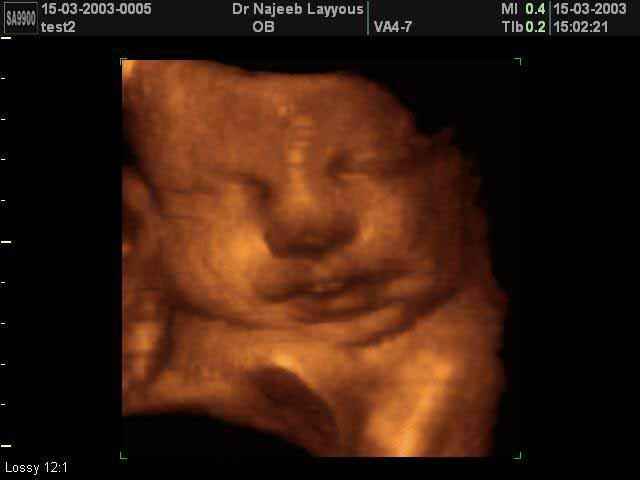

3D Fetal Face Ultrasound Scan Photos